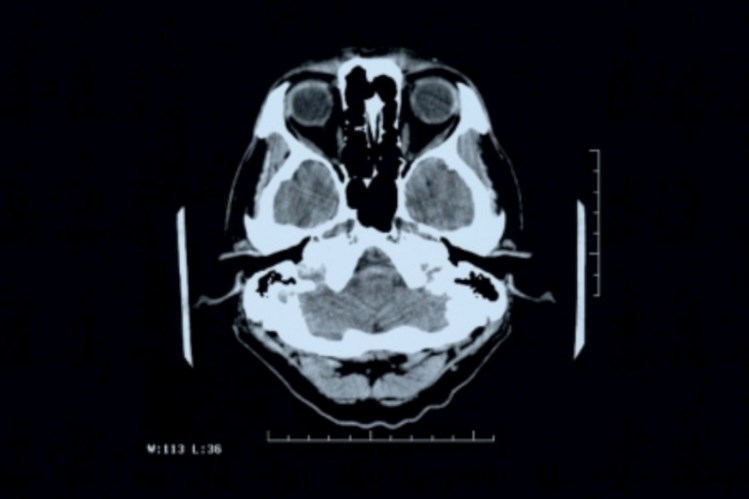

A beta-amilóide vai-se acumulando no cérebro e formando placas, que destroem os neurónios e degradam progressivamente as funções corporais em geral. Não se conhecem as causas exactas da doença de Alzheimer, que inicialmente tem como sintomas a dificuldade em recordar as memórias recentes porque a acumulação das placas provoca as primeiras lesões nas regiões cerebrais envolvidas na formação de novas memórias. À medida que a doença progride, outras regiões do cérebro são afectadas pelos agregados de beta-amilóide. Só depois da morte do doente é que se comprova a doença, através da análise de amostras do cérebro, para verificar a presença das placas.